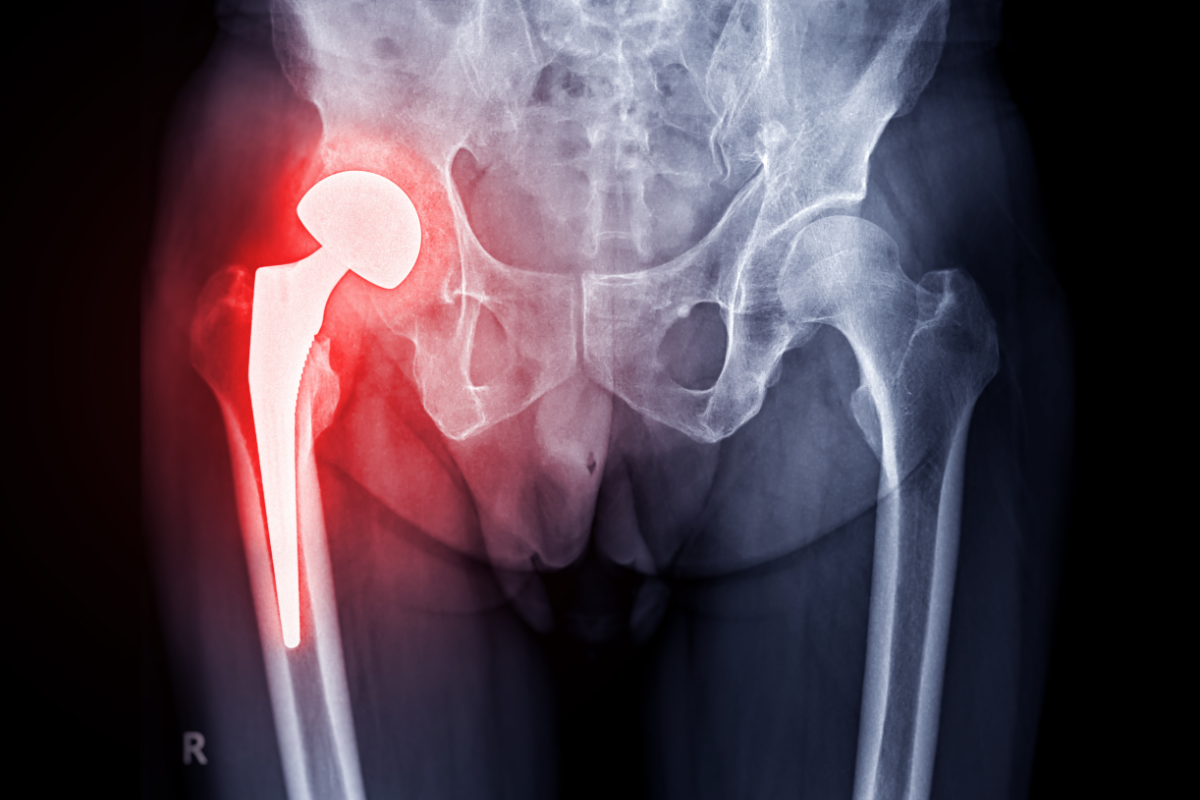

Specialisti in chirurgia ortopedica di anca e ginocchio

Cora Medical Group nasce dalla collaborazione tra tre specialisti in Ortopedia e Traumatologia con esperienza consolidata nella chirurgia articolare di anca e ginocchio.

Il gruppo è specializzato nella chirurgia protesica e ricostruttiva, con un approccio orientato alla personalizzazione del trattamento e al recupero funzionale rapido del paziente.

L’attività clinica si basa sull’integrazione tra competenze chirurgiche avanzate, tecniche mini-invasive e protocolli innovativi, con l’obiettivo di ridurre il dolore post-operatorio e favorire un ritorno precoce alle attività quotidiane e sportive.